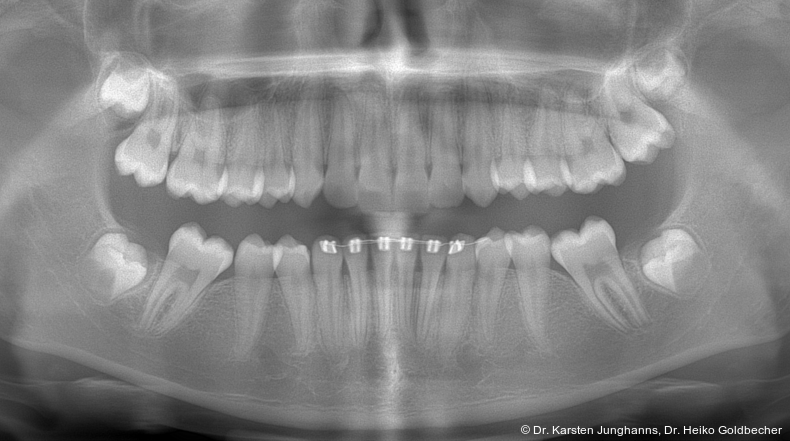

Eine Patientin stellte sich im Alter von neun Jahren erstmals vor. An den ersten Molaren des Unterkiefers wurden vom Hauzahnarzt eine MIH diagnostiziert (Abb. 1a) und die Zähne als nicht erhaltungsfähig eingestuft. Die beiden ersten Molaren wurden hemiseziert und der distale Anteil extrahiert. Gut zu erkennen ist auf dem OPG die annähernd achsengerechte Mesialisierung der zweiten Molaren sowie die Aufwanderung der Zahnkeime der dritten Molaren (Abb 1b: ca. 1,5 Jahre nach Hemisektion). Noch vor Durchbruch der zweiten Molaren in die Mundhöhle wurde auch der mesiale Anteil entfernt. Der spontane Lückenschluss erfolgte innerhalb der nächsten anderthalb Jahre (Abb. 1c). Die endgültige Achsstellung kann nach Ausdehnung der Teilmultibandapparatur eingestellt werden.